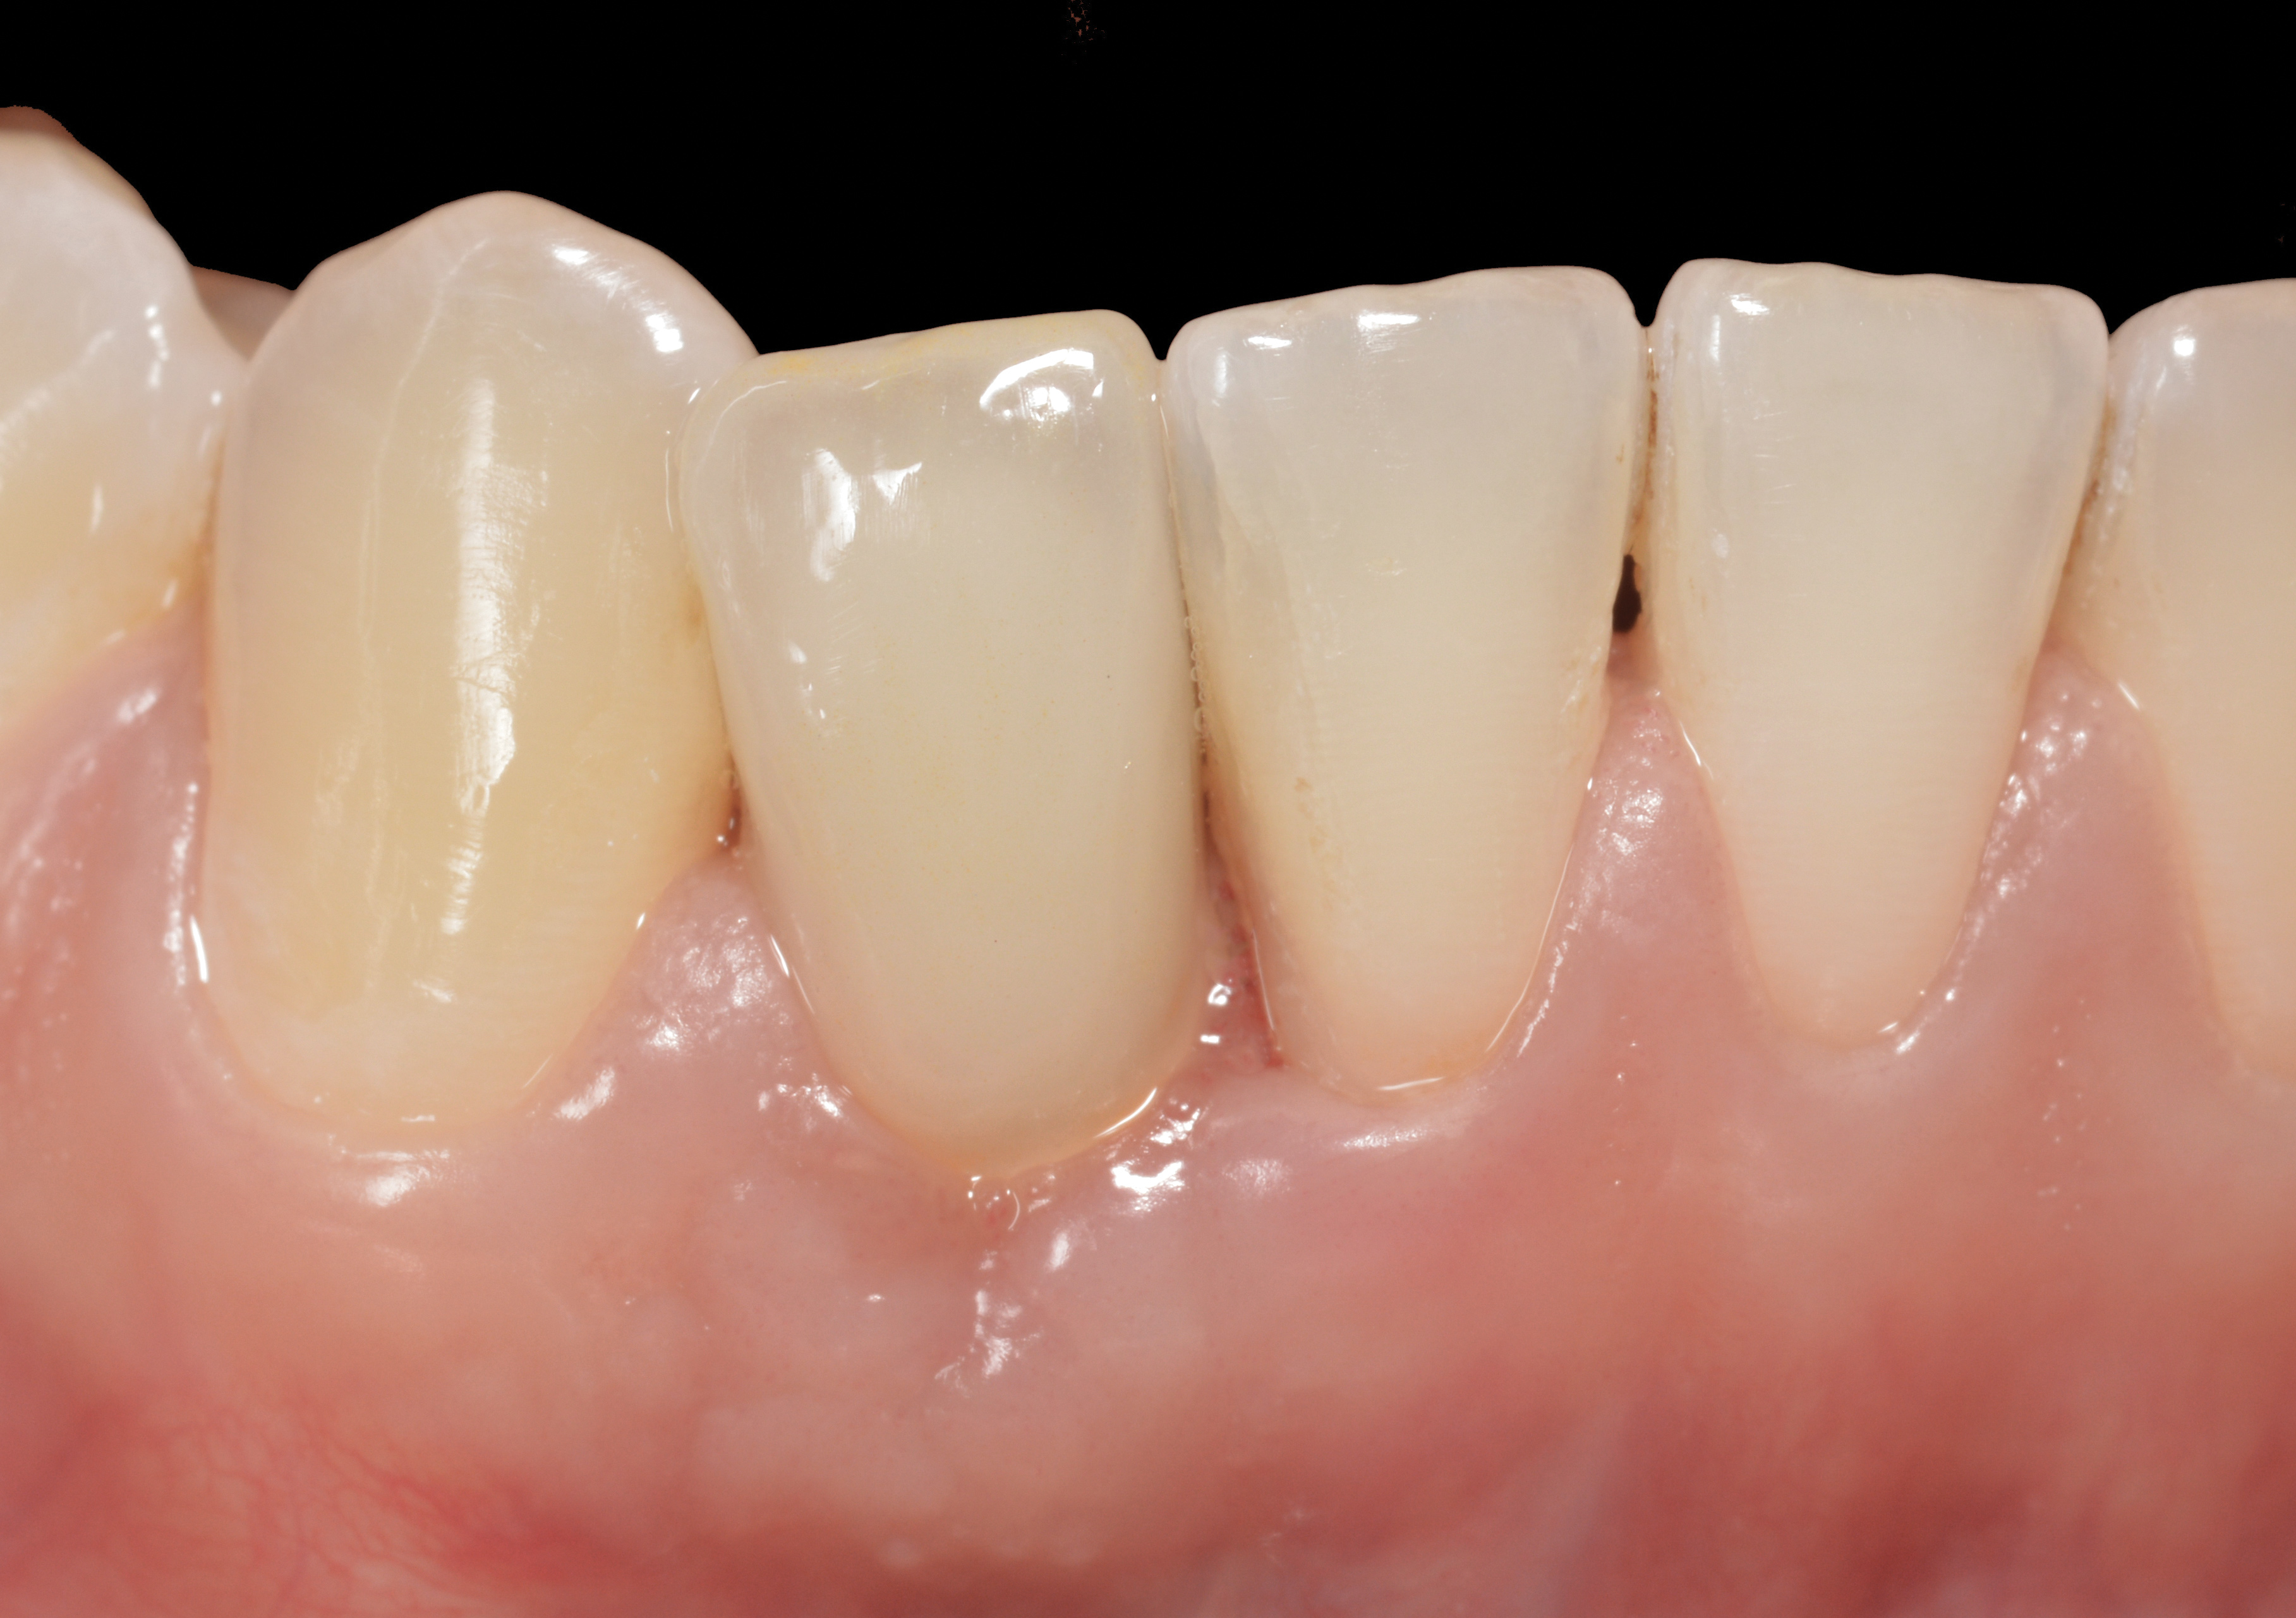

Fig 26. Nine-month follow-up showing a 3-mm probing depth and an absence of bleeding on the buccal of treated implant No. 19.

Figure 26

Fig 27. Seventeen-month follow-up showing keratinized gingiva at the free gingival margin, resolution of the recession defect and deepening of the vestibule. Fig

Figure 27

28. Seventeen-month post-treatment radiograph demonstrating bone close to the implant approximation and almost complete osseous fill of the original infrabony defect.

Figure 28